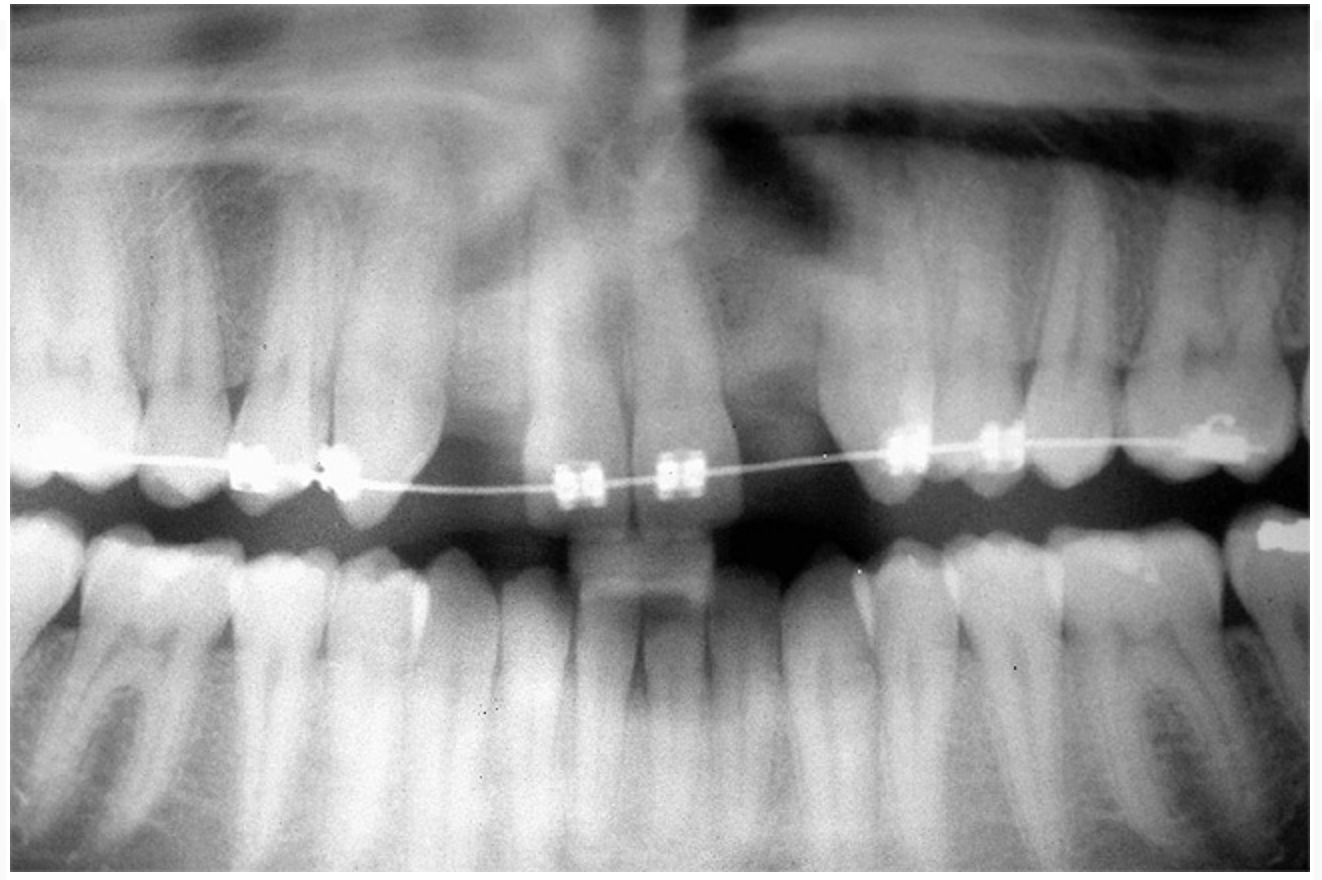

Based upon the intraoral examination and periapical radiographs, additional orthodontic intervention was recommended to move and rotate the roots to gain enough space for implant placement. This information was conveyed to both the parents and to the treating orthodontist. After several additional months, a panoramic radiograph was provided by the orthodontist to evaluate the distance between the clinical crowns and tooth roots (Figure 3). The lack of sharpness, definition, and radiographic artifacts made it impossible to determine whether implants could be successfully placed based on the 2D panoramic image. This diagnostic predicament was discussed with the patient and his parents, and it was suggested that a CT scan would be necessary to accurately assess the bone topography and spatial orientation of the adjacent roots. The parents agreed, and the patient was given a prescription for a CT scan study at a local radiology center.

Figure 3  After orthodontic therapy, the radiograph did not provide enough diagnostic information to determine if implants could be placed.

Figure 3